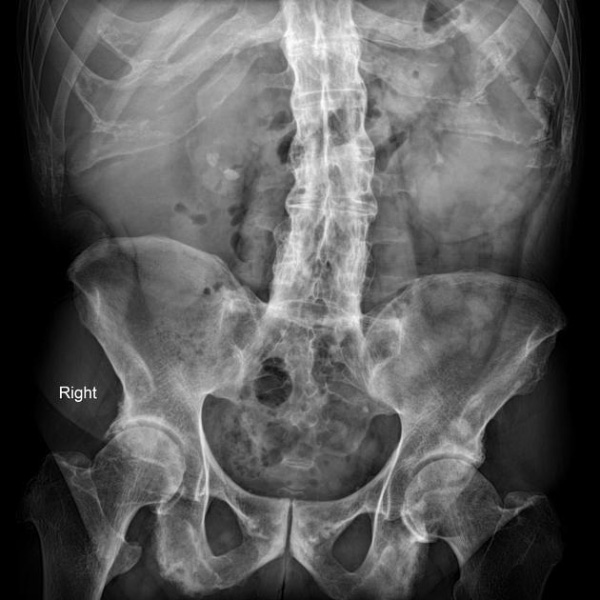

Chụp X-quang là phương pháp chẩn đoán hình ảnh viêm cột sống dính khớp được thực hiện đầu tiên giúp phát hiện các dấu hiệu viêm khớp cùng chậu, dính khớp cột sống và các thay đổi xương khác:

Hình ảnh X-quang viêm cột sống dính khớp có thể cho thấy các dấu hiệu như xói mòn xương, hình vuông hóa đốt sống, cầu xương (syndesmophytes) và dính khớp. Tuy nhiên, cần lưu ý rằng X-quang có độ nhạy hạn chế trong giai đoạn sớm của bệnh, khi các tổn thương viêm chưa gây ra thay đổi cấu trúc xương rõ ràng.

Sau đây là một số hình ảnh viêm cột sống dính khớp trên X-quang: